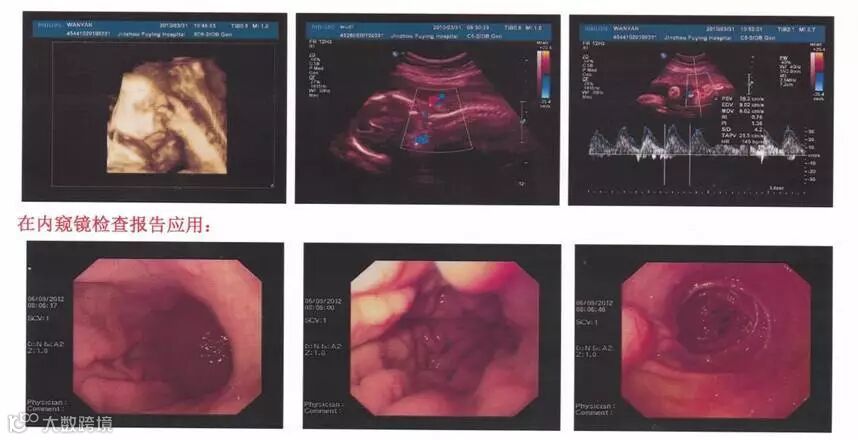

效果展示

原图(电脑截取)

格之格彩超输出专用彩鼓打印实拍

非彩超输出专用彩鼓打印实拍

由图可见,用格之格彩超输出专用彩鼓打印出来的效果更接近原图,没有偏色的情况出现。当然,格之格能做的,还有更多......